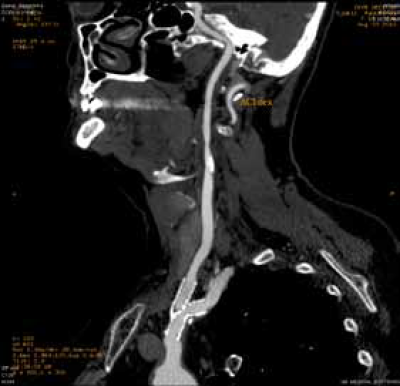

Perkutana transluminalna angioplastika sa stentom zbog aterosklerotične stenoze (90%) desne subklavijalne i desne vertebralne arterije

Dislokacija aterosklerotičnog plaka pri implantaciji aortnog stent grafta, sa stenozom leve zajedničke karotidne arterije u koju je transponirana leva subklavijalna arterija u sklopu hybrid procedure.

Dilatacija orificijuma leve zajedničke arterije sa implantacijom stenta.